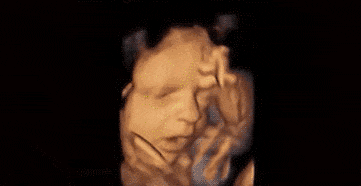

第4张图:做鬼脸

很多妈妈做B超时,会发现宝宝好像在“做鬼脸”,比如张大嘴、咧嘴像在笑。其实那可能是宝宝在打哈欠,或是用力吮吸羊水。因为五官还没完全长开,表情就显得特别有趣。